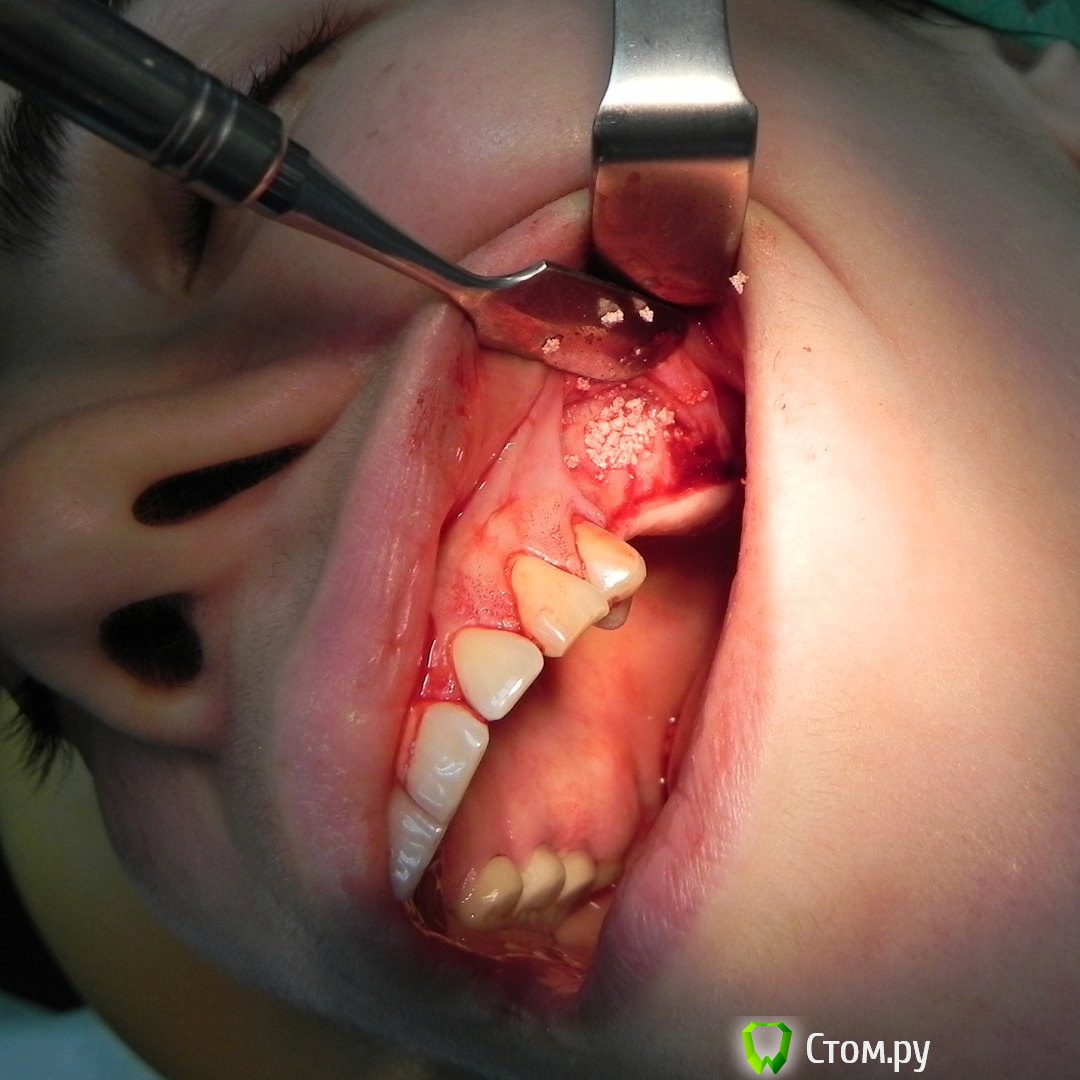

Kostoprav Опубликовано 30 мая, 2015 Автор Поделиться Опубликовано 30 мая, 2015 все работает, чистая синтетика без ауто! это не единичный случай. 2 Ссылка на комментарий